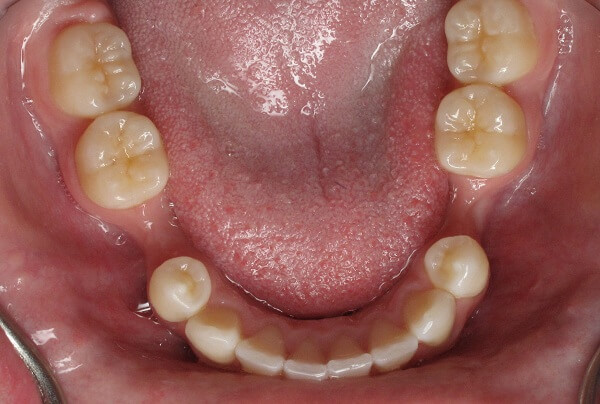

Mất răng dù 1 hay nhiều răng cũng sẽ ảnh hưởng đến chức năng ăn nhai hoặc thẩm mỹ, đặc biệt nếu mất răng lâu năm không được phục hình còn có thể khiến các răng xô lệch, sai khớp cắn hay tiêu xương hàm. Tuy hệ quả của mất răng là không hề nhỏ nhưng vì một lý do nào đó mà có rất nhiều người để tình trạng mất răng lâu năm xảy ra. Vậy mất răng lâu năm có trồng được không và phương pháp nào hiệu quả mời các bạn cùng theo dõi bài viết dưới đây.

Răng số 6 là chiếc răng hàm mọc ở độ tuổi khoảng từ 6-8 tuổi, được tính từ vị trí răng cửa đếm vào. Răng 6 là một chiếc răng hàm vĩnh viễn có chức năng quan trọng trong bộ máy nhai giúp cắn, nghiền nát thức ăn. Vì chỉ mọc 1 lần, không có răng thay thế nên việc chăm sóc, giữ gìn răng 6 là rất cần thiết. Nhưng chẳng may vì một lý do nào đó như: tai nạn, chấn thương, bị sâu phải nhổ bỏ…khiến răng 6 của bạn bị mất thì việc phục hình, trồng lại một chiếc răng mới là rất cần thiết.

Tiêu xương răng là một trong những hậu quả nghiêm trọng sau khi mất đi một hay nhiều răng, gây ảnh hưởng đến thẩm mỹ, chức năng ăn nhai giảm sút và cản trở việc trồng lại răng giả sau này. Phương pháp trồng răng mất bằng chân răng nhân tạo implant là phương pháp phục hình răng hiện đại nhất hiện nay với khả năng hạn chế đến mức tối đa hiện tượng tiêu xương hàm diễn ra sau mất răng.